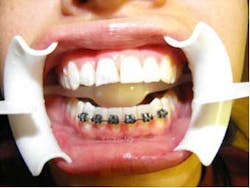

She came to me for an orthodontic consultation. She was 24 years old and hoping to marry her then-boyfriend at some point, but she didn't like her smile; she felt it was unattractive. So we gathered her orthodontic records and pointed out to her that it appeared she had either a supernumerary tooth or over-retained primary tooth between her upper centrals. Along with this, she also had some minor crowding on her lower teeth. She had a Class I molar relationship that I hoped to maintain.

Bleaching — We debanded the upper and performed a Zoom bleaching up top. At that time we also impressed to make a lower bonded lab-fabricated retainer. (I know we should do this in-office.)